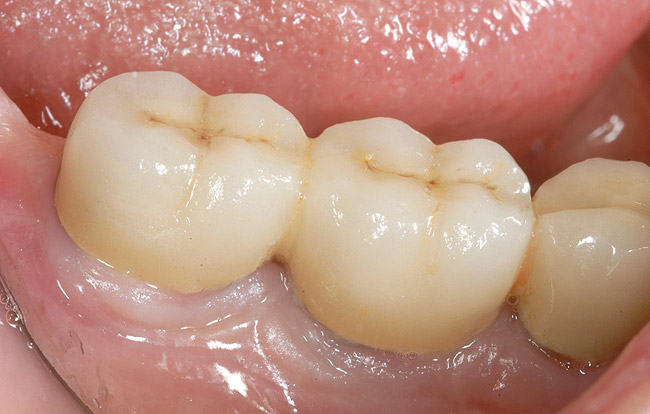

Figure 12  Proper gingival contours following placement of the implants and subsequent hard-tissue graft.

Figure 12

Patient expectations remain extremely critical. The treatment options must be able to meet these expectations, otherwise tooth replacement of the edentulous area with dental implants should not be attempted. A set of mounted casts in centric relation with a full contour diagnostic wax-up, including the hard- and soft-tissue deficits, is mandatory prior to initiating treatment. This is beneficial in accessing the edentulous space and communicating the information concerning the edentulous defect with the laboratory technician, the implant surgeon, and most importantly, the patient. In addition, CBCT can also be extremely helpful in diagnosing the edentulous site 3-dimensionally and providing vital information to the surgeon prior to implant placement (Figure 9). Only after the diagnosis and treatment plan is fully understood by all parties should the treatment be initiated. In many situations, hard- and soft-tissue grafts are necessary in order to reconstruct the edentulous site as near to its original contours as possible (Figure 10 through Figure 12). This will significantly enhance proper positioning of the implant for prosthetic needs and help to increase the prognosis for an esthetic result.27 At the time of implant placement, a surgical template should be used to help ensure that the implant is placed in the proper position. The surgical template can be fabricated from the diagnostic wax-up or generated from planning software using the Digital Imaging and Communications in Medicine data obtained from the CBCT. The esthetic result is generally dictated at the time the implant is placed, hence the need for such a detailed assessment.